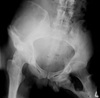

42

What is the most likely diagnosis? What bones are involved?

AVN of femoral head